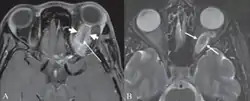

Магнітно-резонансну томографію (МРТ) використовують для візуалізації невритів, пухлин, у випадку передньої ішемічної нейропатії, у випадку внутрішньочерепної гіпертензії. При невритах у T-2 режимі можна побачити набряклий нерв із підвищеним сигналом. Чутливим є використання T-1 режиму із супресією жиру та використанням гадоліну як контрастного агента.[75] У такому випадку також відзначатимуть посилення сигналу.[75] При менінгіомі у T-1 режимі пухлина буде ізо- або гіподенсною щодо нерва, у T-2 режимі — ізо- або гіперденсною[76]. Гліома при використанні МРТ виглядає як мішкоподібне розширення нерва, гіподенсне у T-1 режимі та гіперденсне у T-2 режимі[77].

B) Гліома зорового нерва (стрілочками показане розширення власне зорового нерва).

Найчастішою пухлиною, яка походить з клітин нерва, є гліома, яка зазвичай доброякісна. Найчастіше вона виникає у перші десять років життя. Більшість пухлин виникає спорадично та лише з одного боку, проте гліома зорового нерва може бути пов'язана з нейрофіброматозом I типу. В останньому випадку вона може проявлятися як двобічний процес. Поступово виникає однобічне зниження гостроти зору, обмеження полів зору, екзофтальм, косина, больові відчуття відсутні. При огляді очного дна видніється набряклий диск зорового нерва. Через стискання нерва може виникнути його атрофія, оклюзія центральної вени сітківки та неоваскулярна глаукома.[111][112]